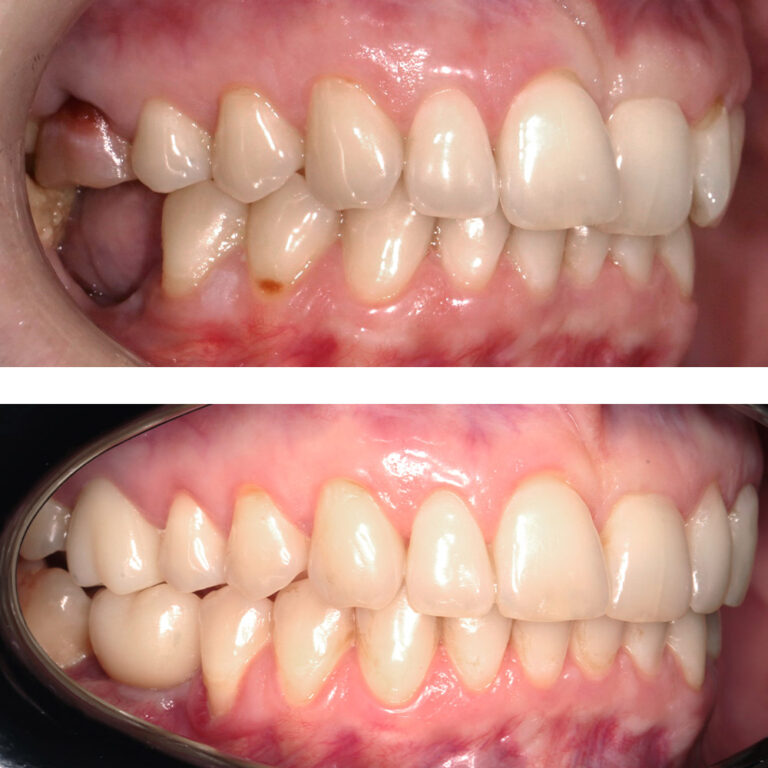

Кейс 21

ДО

ПОСЛЕ